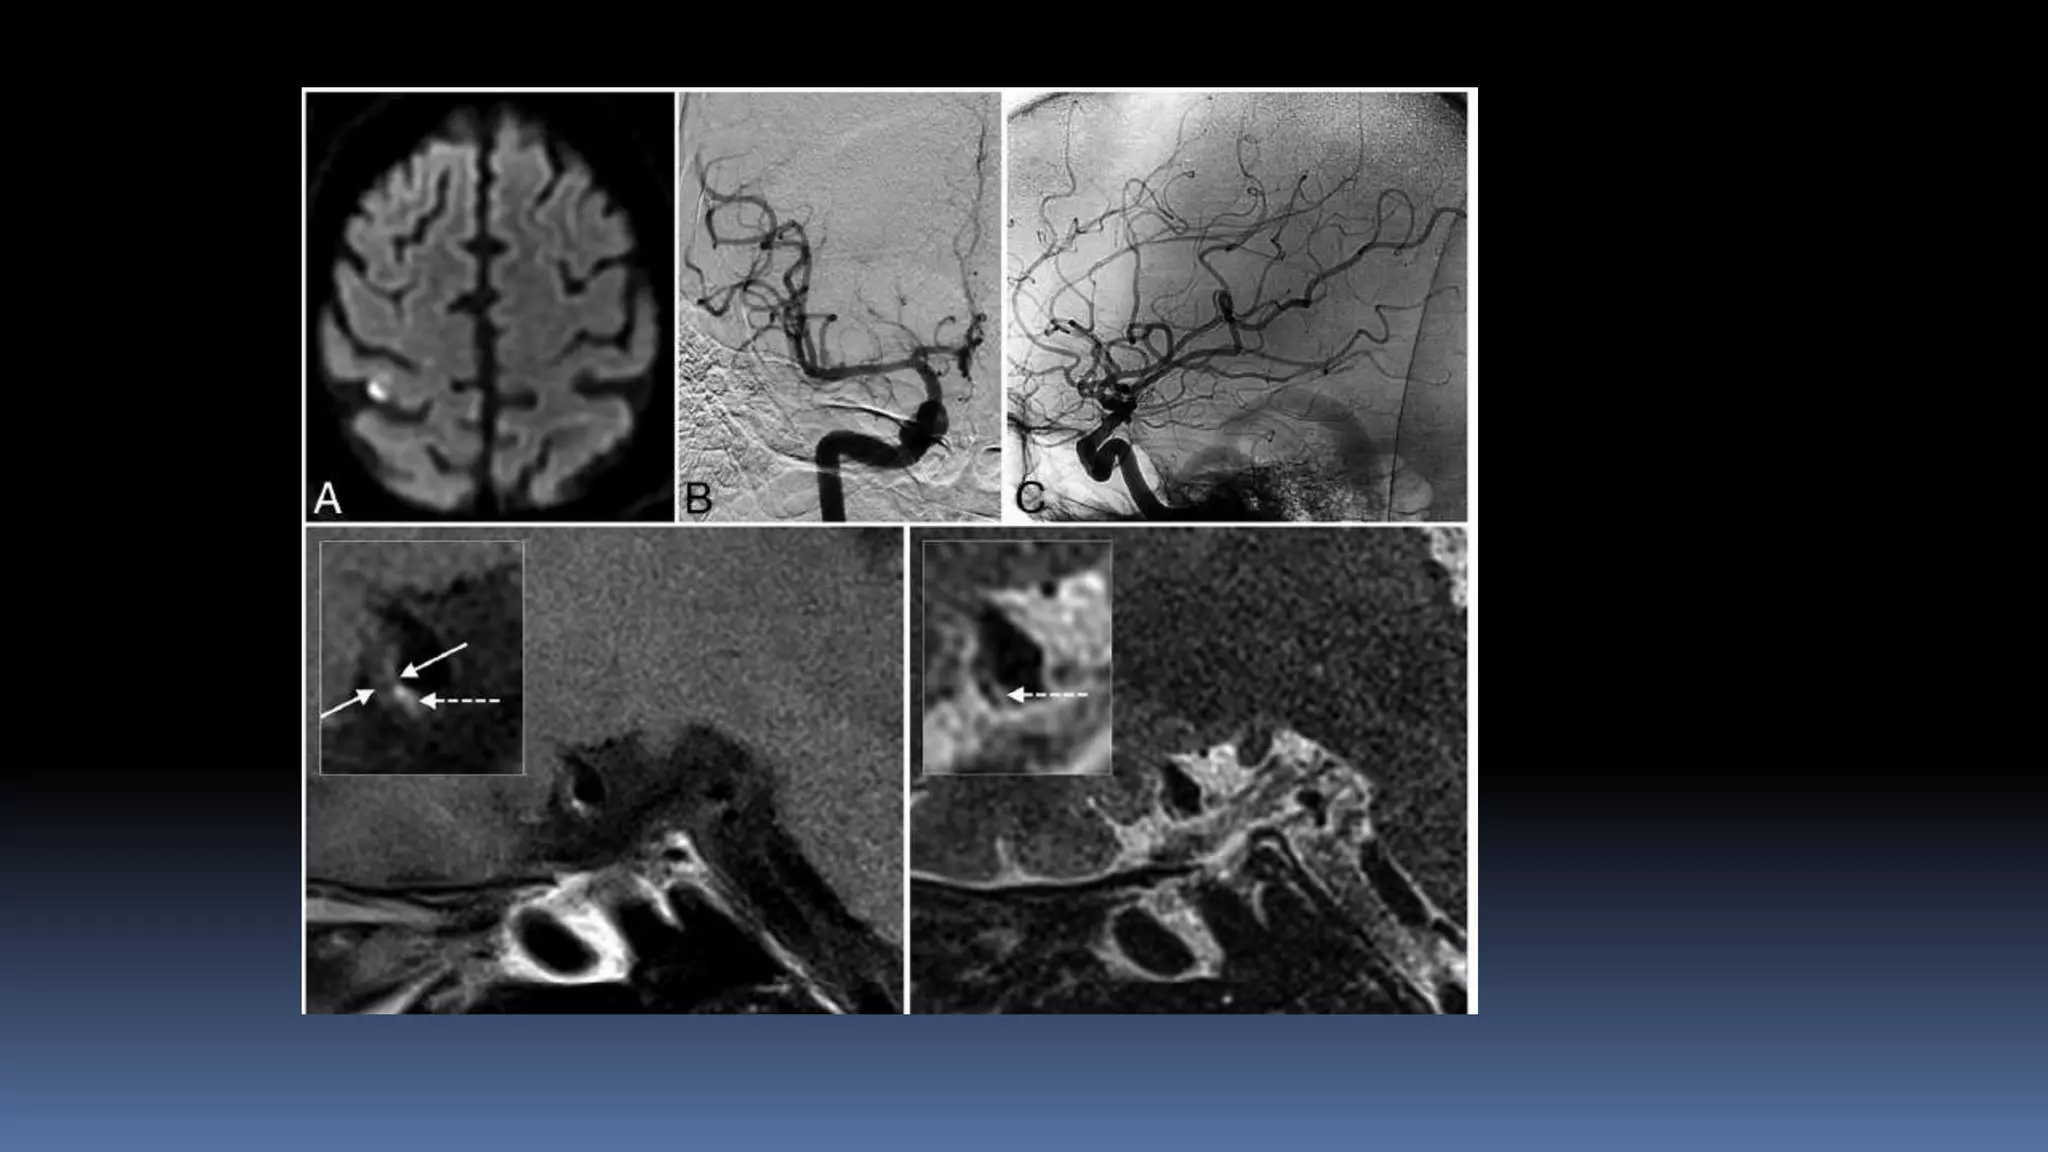

•68/M, DM, HTN, CAD, underwent PTCA to LAD

•Admitted for surgery of aortic stenosis.

•Double anti-platelets was stopped

•Patient developed acute onset right side weakness

with aphasia.

IV- tPA given, no improvement

Futile recanalization….

 Left hemiplegia, left UL and LL 0/5

 5:14AM

6:22AM

8:07 AM

Patient made gradual recovery

Left LL 4/5 and UL 3/5 - 30 day follow up mRS at 90

days- 0

Patient presented with in 2 hours

Futile IV tpa